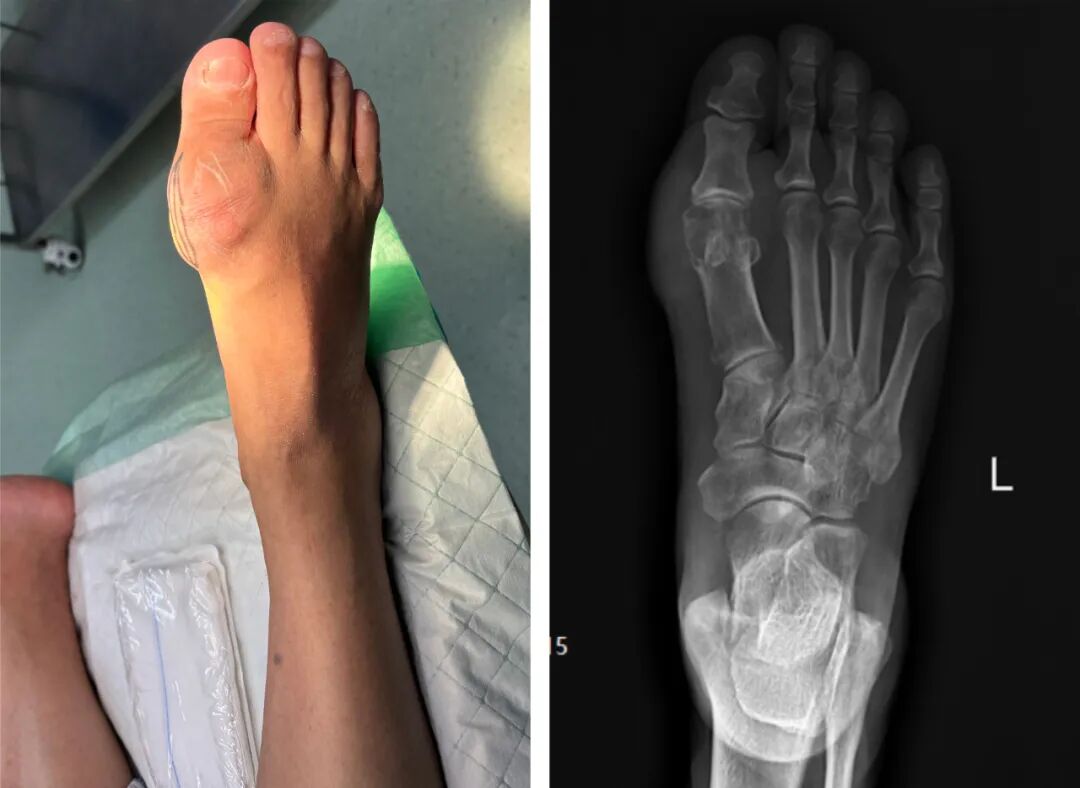

10年前,张大爷无意发现左足内侧有一个包块,由于不痛不痒,便未曾引起重视,但随着时间的推移,包块越来越大,肉眼可见已有鸽蛋大小,且上月开始包块无缘无故出现压痛情况,鼓起包块位置的皮肤发红发亮,仿佛随时会破裂一般,行走时疼痛难忍,严重影响了日常生活。为求进一步治疗,在邻居的推荐下急忙来到我院外科,找到李方勇主任。

"医生,我实在受不了了,这脚跟火烧一样疼,"张大爷的声音都在发抖。李主任立即为张大爷进行相关检查,结果令人震惊:他的尿酸值竟高达643μmol/L(正常男性尿酸值应在150~416μmol/L),X光片显示左脚关节处多发结石,确诊为左足痛风石。

综合各种因素,经外科团队的精心安排,昨日,顺利开展手术:术中大量白色粉末状物质包裹着关节,软骨组织已经被侵蚀得面目全非。这些"石头"虽然置底柔软,但与周围组织紧密粘连,稍有不慎就会损伤神经和血管。最终耗时1个半小时,成功帮助张大爷清除痛风石,术后,张大爷的疼痛明显缓解,经过一段时间的康复治疗和严格的血尿酸控制,目前的关节功能逐渐恢复,生活质量得到了显著提高。